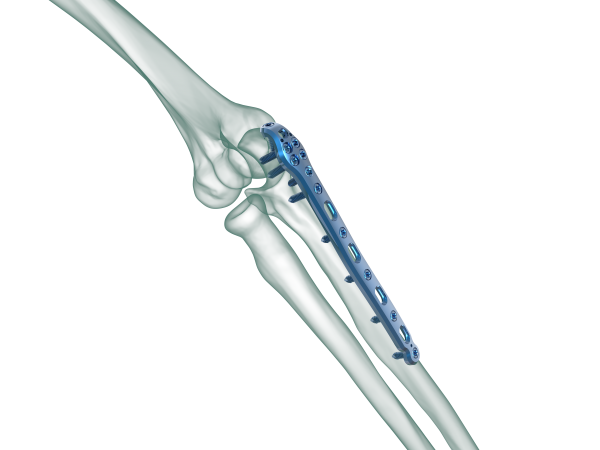

TRUE LOCK Olecranon Anatomic Plates are precontoured for anatomic fit. No need to bend during teh surgery.

Elongated Combi hole in the neck and shaft facilitate plate adjustment and allow locking or compression options.

Long proximal extension and multiple screw options to secure small olecranon fragments to help neutralize the forces of the triceps muscle.

Kirschner wire holes accept Kirschner wires (up to 1.5 mm) to temporarily fix the plate to the bone, to temporarily reduce articular fragments, and to confirm the location of the plate, relative to the bone.